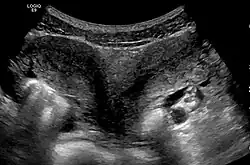

Ultrasound showing didelphys | |